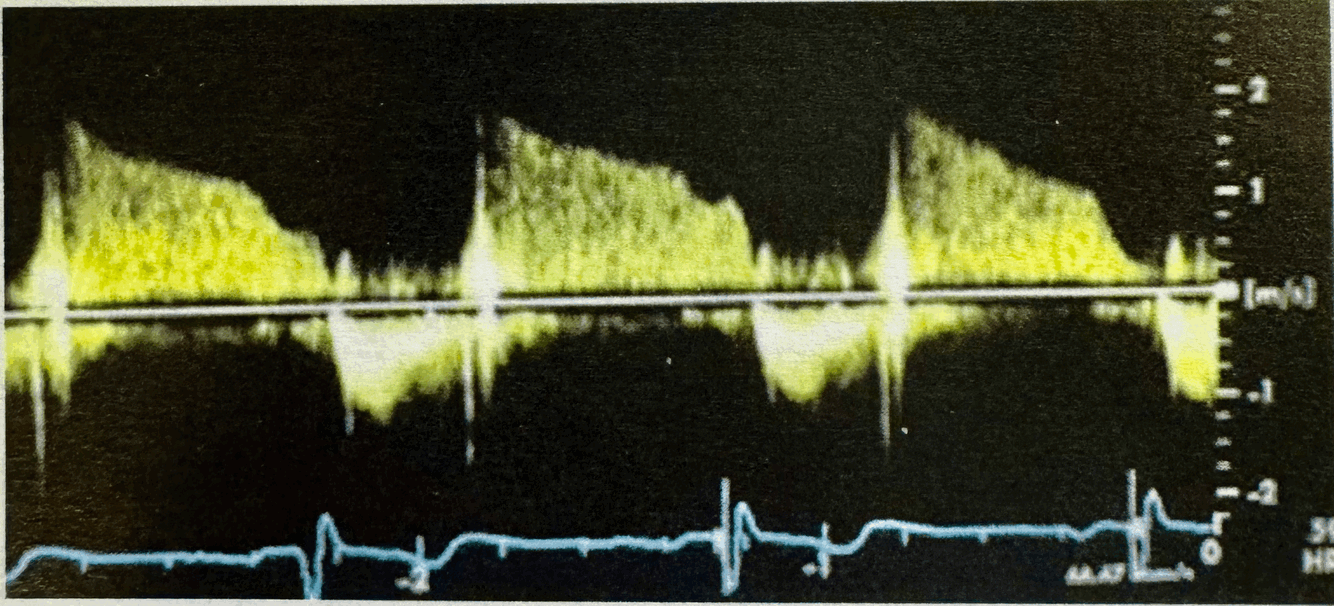

Q

What normal flow pattern is this and in what view?

A

descending AO Thoracic, SSN/Subcostal